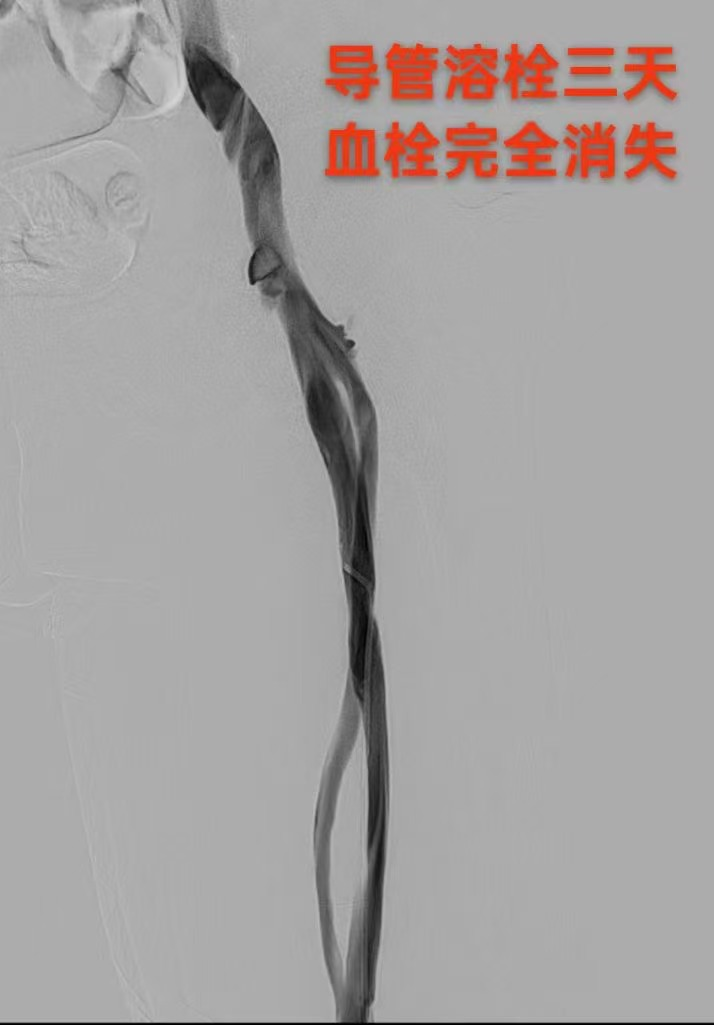

圖一為下肢血栓形成影像圖片 圖二為與圖一同部位經(jīng)過治療后血栓消失照片(圖片來源網(wǎng)絡(luò),如有侵權(quán)聯(lián)系刪除)

歸處一:血栓溶解、吸收或軟化;水管里新鮮的雜質(zhì)會隨著水流和壓力的增強稀釋溶解,靜脈血栓同理也會隨著血容量的增加及自身纖溶系統(tǒng)而稀釋或者溶解。新近形成的血栓,血栓內(nèi)會產(chǎn)生纖維蛋白溶解酶等,可以促使血栓軟化并逐漸溶解,血栓是可以自行溶解的。而血栓的溶解快慢或者程度,取決于血栓的大小和新舊程度,血栓越新鮮,自身基礎(chǔ)因素越好血栓越容易溶解。血栓形成的同時,纖溶系統(tǒng)也不同程度地被激活,血栓中的纖維蛋白吸附大量纖溶酶,也可使血栓溶解軟化;血漿內(nèi)正常存在的纖溶酶原被纖溶酶原激活劑激活成纖溶酶,與纖維素結(jié)合的纖溶酶可將纖維蛋白溶解。小而新鮮的血栓在特定情況下可完全溶解,這就是部分血栓患者,如下肢肌間靜脈血栓,單純使用藥物抗凝治療,就能取得很好效果的原因之一。但較大的血栓則不能被完全吸收從而被機化,或由于部分發(fā)生軟化,被血液沖擊可形成碎片狀或整個脫落,形成栓子隨血流運行,引起栓塞。這類似水管里的淤泥等雜質(zhì)較多時,一些雜質(zhì)會被稀釋或溶解,還有一些會松動或脫落,然后隨著水管里的水流被沖走。溶解脫落的血栓會隨著血液流到其它組織器官中,然后卡在與血栓大小相應(yīng)的血管中造成血栓栓塞。這也是下肢深靜脈血栓會順著血管方向脫落堵塞肺部的血管造成肺栓塞的原因之一。就像城市停水后,我們會發(fā)現(xiàn)水龍頭里會有泥水的情況,就是因為水管里的淤泥等雜質(zhì)隨著水流和壓力的恢復(fù),分散溶解在水中流到千家萬戶(毛細血管)一樣。